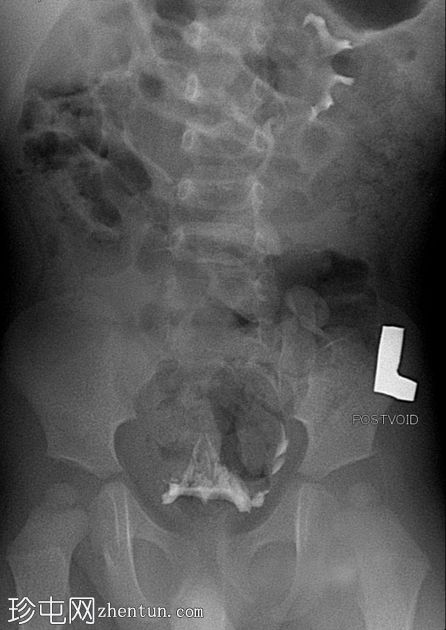

正位片(含Foley导尿管球囊)

排尿后影像

可见脐尿管开口通畅;在充盈期,造影剂经脐尿管自由流出,导致膀胱充盈不足。经脐尿管开口置入Foley导尿管并充盈球囊;然而,造影剂持续渗漏,膀胱充盈仍然不足。